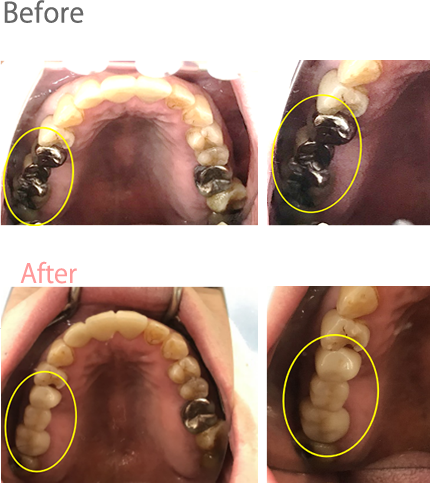

女性Kさん 50代(オールセラミック冠)

主訴

金属アレルギーかもしれないので、相談したい。

治療内容

掌蹠膿疱症で約10年程悩まされていたそうです。皮膚科に通院していたものの、改善されず、皮膚科の先生に「もしかすると口の中の金属が原因かもしれない。」とアドバイスされ、来院されました。口腔内には、多数の金属がありました。原因と考えられるものを取り除くことが第一と考え、ひとつずつ金属を使わない材料で治療しなおしました。

所感

口腔内の金属を徐々に取り除いて約半年が経過したころより、少しずつ皮膚の症状の改善が見られはじめたそうです。今年(2019年)に入り、更に改善が見られ、「歯科通院中も皮膚科にも通っていたが、歯科に通院する前は、皮膚科で出された薬では良くならなかったので、今あらためて考えると、やはり口腔内の金属が原因ではなかったのかなぁ…。」と、とても明るい表情でお話ししてくださいました。皮膚科に行ってもなかなか治らない皮膚症状のすべてが口の中の金属であるとは考えませんが、金属のアクセサリーをつけてかゆみ赤みなどが出る方、なかなか治らない皮膚症状がある方は、原因の一つと考えられるお口の中の金属を取り除いた方が良いことは、確かだと思います。

オールセラミック冠14本:¥80,000×14本=¥1,120,000(税別)